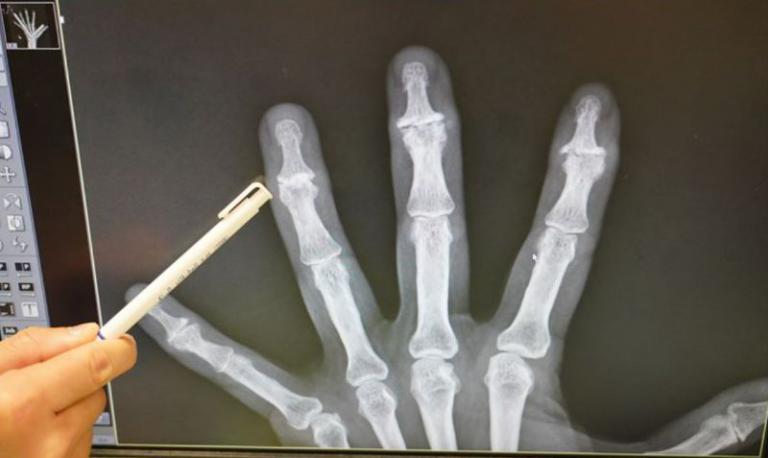

兩位均是近幾年數個手指(第二至第五隻手指)遠端指間關節腫痛現象,尤其抓提重物異常疼痛,抓握力下降,今年開始手指中段(近端指間關節腫痛),也開始腫痛,診療時X光可見關節狹窄與骨刺增生,但無骨頭侵蝕的現象,告知罹患手部退化性關節炎時,都不免疑惑手部也會退化?如何治療? 如何保養?

▲X光可見手指遠端關節狹窄與骨刺增生。(圖/記者蔣彤雲攝)

曾能祥醫師說,全身上下的關節都有罹患退化性關節炎的機會,除了膝關節、髖關節退化外,手部的退化性關節炎也很常見,尤其以手指的遠端指間關節和大拇指的掌指關節、掌腕關節最常發生。